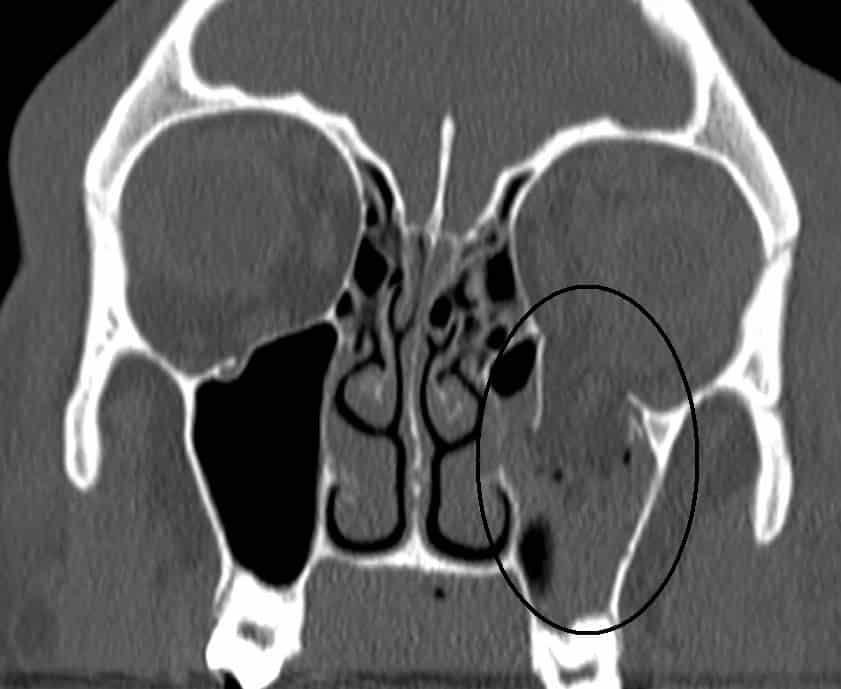

Fig 1.3 - CT scan of a blowout fracture of the eye, through the inferior wall. The contents of the orbit have herniated into the maxillary sinus.

CT scan of a blowout fracture of the eye, through the inferior wall. The contents of the orbit have herniated into the maxillary sinus.

• Orbital rim fracture – This is a fracture of the bones forming the outer rim of the bony orbit. It usually occurs at the sutures joining the three bones of the orbital rim – the maxilla, zygomatic and frontal.

• ‘Blowout’ fracture – This refers to partial herniation of the orbital contents through one of its walls. This usually occurs via blunt force trauma to the eye. The medial and inferior walls are the weakest, with the contents herniating into the ethmoid and maxillary sinuses respectively.

Any fracture of the orbit will result in intraorbital pressure, raising the pressure in the orbit, causing exophthalmos (protrusion of the eye). There may also be involvement of surrounding structures, – e.g haemorrhage into one of the neighbouring sinuses.